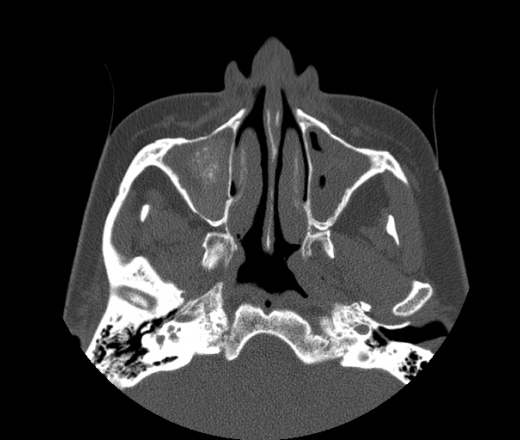

Полипозный этмоидит

Полипозный этмоидит 110 фото